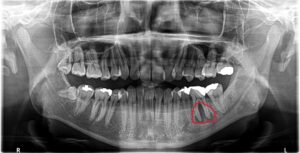

初診時レントゲン

下顎左側第一大臼歯(赤丸)に親指の頭ぐらいの大きさの根尖病変が認められます。

口腔内には舌側に瘻孔(膿の出口)が認められます。